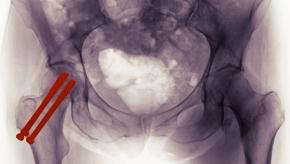

Read ArticleAge and Comorbidity Contribute to Higher Death Risk Following Hip Fracture Surgery

Patients undergoing surgery for a hip fracture appear to have higher death rates than those having elective total hip replacement.